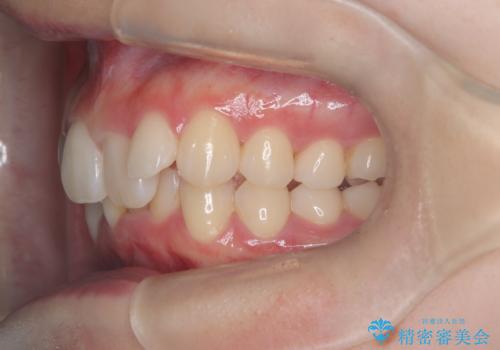

- 患者様は、下顎前歯のガタつきを改善したいとのことで来院されました。診察の結果、スペース不足により前歯が重なっている状態でした。抜歯をせずに並べると前歯が前方に突出してしまうため、下顎の前歯を1本抜歯し、インビザラインで矯正する治療計画を立てました。できる限り追加のアライナーを使用せずに治療を完了できるよう、初回の治療計画を慎重に設計しました。

下顎前歯を1本抜歯し、歯列のスペースを確保。その後、インビザラインを用いて計画通りに歯を移動させ、噛み合わせも整えました。患者様の協力もあり、ゴムかけなどを適切に行い、予定通り1年で治療を完了。追加アライナーを使用することなく、計画通りに治療を終えることができました。患者様からは「思ったより早く終わり、仕上がりにも満足している」と喜びの声をいただきました。